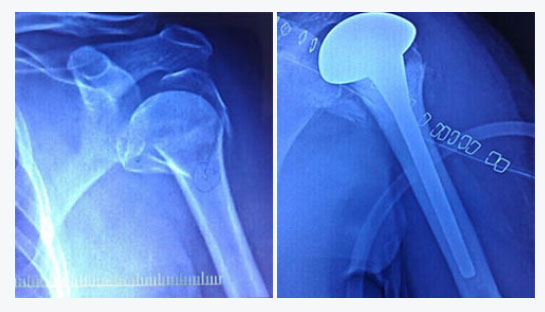

Shoulder replacement surgery is most commonly used for severe degenerative joint disease (osteoarthritis) or rheumatoid arthritis of the ball-and-socket joint. When the smooth surfaces (cartilage) of the ball and socket become rough, they rub against each other rather than glide. This rubbing causes pain and stiffness that limits daily activities, as well as interferes with sleep. Other indications that justifies shoulder replacement are severely communited fracture of proximal humerus which cannot be reconstructed and avascular necrosis of humeral head. A shoulder replacement is performed to alleviate shoulder pain. It also helps to improve the range of motion of your shoulder joint, which also improves your function and the quality of your life.

Here, the ball (humeral head) of the shoulder joint is replaced with an implant that includes a stem with a smooth, rounded metal head. The socket (glenoid) is replaced with a smooth, specialized plastic that is cemented into place.

Here, the normal structure of the shoulder is “reversed.” The ball portion of the implant is attached to the scapula (where the socket normally is) and the artificial socket is attached to the humeral head (where the ball normally is). This allows the stronger deltoid muscles of the shoulder to take over much of the work of moving the shoulder, increasing joint stability. A reversed procedure is use for patients with a severely torn and compromised rotator cuff. It is also commonly used in revision surgery cases.

Shoulder replacement is performed in the hospital with the help of an experienced, specialized surgical team. The procedure generally takes 2 hours. Afterwards patients stay in the hospital for 3-4 days. To get to the shoulder joint an incision is made on the front of your shoulder. After exposing the shoulder joint, the damaged ends of the bone (humerus and glenoid) are removed. The bone is prepared for the replacement with the artificial joint. The artificial joint is made of metal, usually a titanium or a cobalt-chrome alloy. For a standard shoulder replacement the stem is placed inside the humerus bone. The glenoid component is made of a special plastic (polyethylene). The glenoid is cemented into place. Not all patients require a glenoid component and the final decision to use a glenoid component is made during the surgery. For reverse shoulder replacements the ball is secured to the socket with a press-fit and supplemented with screws. The humeral stem is then press-fit or cemented into place. A high-strength plastic then is placed to act as a spacer between the stem and the ball.